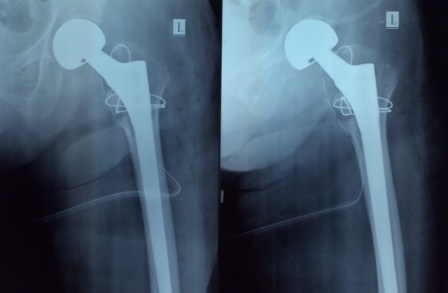

Kết quả chẩn đoán hình ảnh cho thấy bệnh nhân bị gãy liên mấu chuyển xương đùi bên trái. Cùng với tình trạng chấn thương, cụ bà còn mắc nhiều bệnh lý nền như tiểu đường, tim mạch, huyết áp… Cụ đối mặt với nguy cơ không đi lại được, đau nhiều, tắc mạch, loét tì đè, viên phổi, nhiễm trùng đường niệu, suy kiệt dẫn tới tử vong.

Để tránh những biến chứng sẽ xảy đến với người bệnh, các bác sĩ quyết định thực hiện cuộc phẫu thuật thay khớp háng cho cụ dưới sự đồng ý của gia đình. Sau 40 phút khẩn trương, thủ thuật can thiệp thay khớp háng cho người bệnh được thực hiện thành công. 48 giờ sau mổ, cụ bà đã có thể ngồi dậy và nói chuyện với người nhà. BS Nguyễn Hồng Trung, Trưởng khoa Ngoại tổng hợp cho biết: Phẫu thuật thay khớp nhân tạo không chỉ giúp bệnh nhân phục hồi đầy đủ các cơ năng như khớp bình thường của cơ quan vận động mà còn loại bỏ nguy cơ biến chứng.